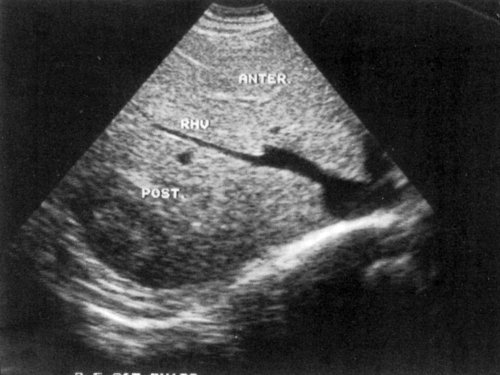

Сегментарное строение печени

Сегментарное строение печени — важная часть ультразвукового исследования, поскольку информация о том, в каком сегменте органа располагается поражение имеет большое значение. Печень может быть разделена печеночными венами следующим образом: правая вена делит правую долю на два сегмента — задний и передний (рис. 10) и левая вена разделяет левую долю на латеральный и медиальный сегменты (рис. 11). Теперь, если мы проведем продольные плоскости через левую, среднюю и правую главные воротные вены (рис. 12), то печень будет разделена на восемь сегментов (рис. 13).

Рис. 10. Подреберный косой срез через правую долю печени позволяет увидеть передний и задний сегменты (эхограмма).

RHV — правая печеночная вена, MHV — средняя печеночная вена, LHV — левая печеночная вена, RPV — правая главная воротная вена, LPV — левая главная воротная вена.

Рис. 13. Печень разделена на восемь сегментов следующим образом: 1 — хвостатая доля, которая ограничена сзади нижней полой веной и спереди главной печеночной бороздой; 2 и 3 — левый латеральный сегмент; 4 — левый медиальный сегмент; 5 и 8 — правый передний сегмент; 6 и 7 — правый задний сегмент.